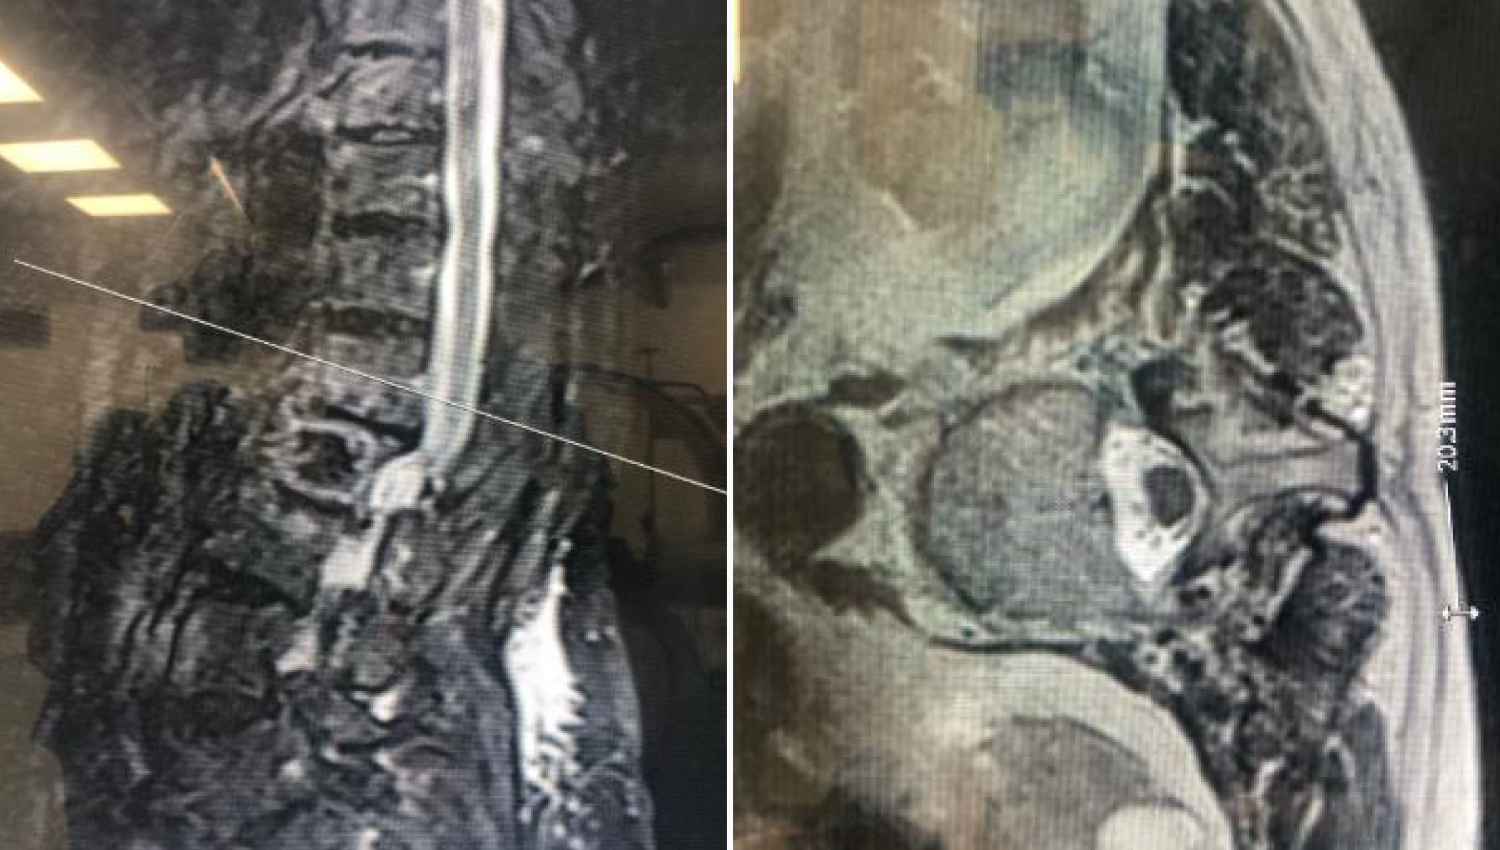

1.Initial radiological view.

2.Imaging of the defect in the spine at the beginning of the operation.